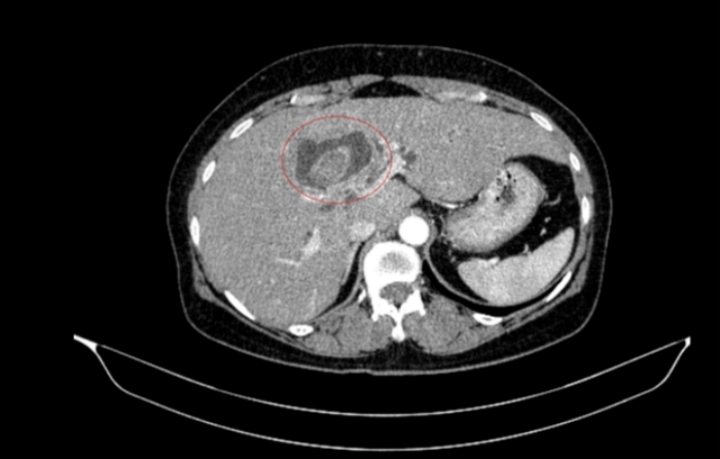

Hình ảnh sỏi đường mật tạo ổ áp xe gan - đường mật gan trái (vòng tròn màu đỏ).